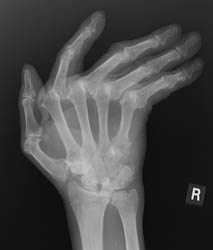

This disease is a bilaterally symmetrical and polyarticular process. Commonly

affected joints of the hand and wrist include the MCP, PIP, any of the wrist

joints, and the distal ulna and radial styloid. The distal interphalangeal

joints are rarely involved.

The earliest signs of the disease process are periarticular soft tissue swelling

due to effusion, tenosynovitis and edema. Joint spaces may actually widen

in the early stages of RA. Periarticular osteopenia can also be seen. Early

articular changes occur at the "bare area" of small joints, which

are not covered by cartilage. These marginal erosions are often first seen

at the 2nd and 3rd MCP and the 3rd PIP articulations.

Advanced signs of RA include diffuse loss of joint space due to loss of cartilage. There can also be marginal or central erosions and severe joint deformities. Subluxations and dislocations may lead to ulnar deviation at the MCP joints and radial deviation at the radiocarpal articulations of the wrists. Erosive changes are also noted at the distal ulna and radial styloid. Joint deformities seen in RA include a Boutonniere deformity (flexion at the PIP joint and hyperextension at DIP joint) and a Swan-neck deformity (hyperextension at the PIP joint and flexion at the DIP joint). In severe cases, there may be radiographic findings of ankylosis at the proximal interphalangeal and metacarpophalangeal joints.